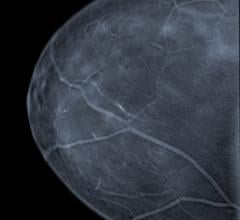

Mammography is a breast imaging technique that uses X-rays to diagnose and locate tumors of the breasts.

Despite decades of progress in breast imaging, one challenge continues to test even the most skilled radiologists ...

Two decades of research on the masking risk of dense breast tissue by mammography screening is indisputable. As the ...